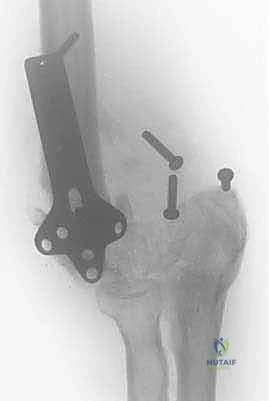

FIG 1 • Radiograph demonstrating dissociation of the forearm from the brachium in a patient with an inadequately treated fracture of the distal humerus with resultant nonunion.